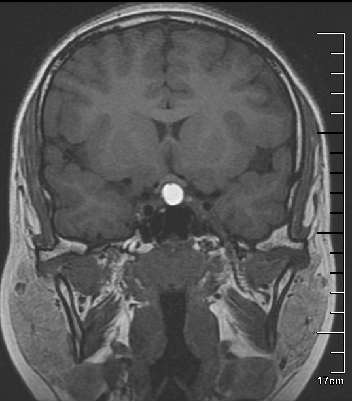

最常见的表现为囊肿在 T1 加权图呈低信号,在 T2 加权图呈高信号,即长 T1 长 T2 信号,其次是短 T1 长 T2 信号,其他信号变化包括等 T1 等 T2 信号、等 T1 短 T2 信号、等 T1 长 T2 信号、短 T1 短 T2 信号号等,囊肿内也可同时呈多种信号变化。

Rathke 囊肿 MR 信号的多样化主要与囊内容物有关,囊内黏多糖含量高是造成 T1 加权图高信号的主要原因。增强扫描囊肿本身不强化,囊肿周围正常的垂体腺组织强化,囊壁及囊内不钙化。

有认为 Rathke 囊肿内有与囊液信号不同的小结节,简称漂浮结节,是 Rathke 囊肿的特征性表现,但这种小结节常难以显示和辨认。